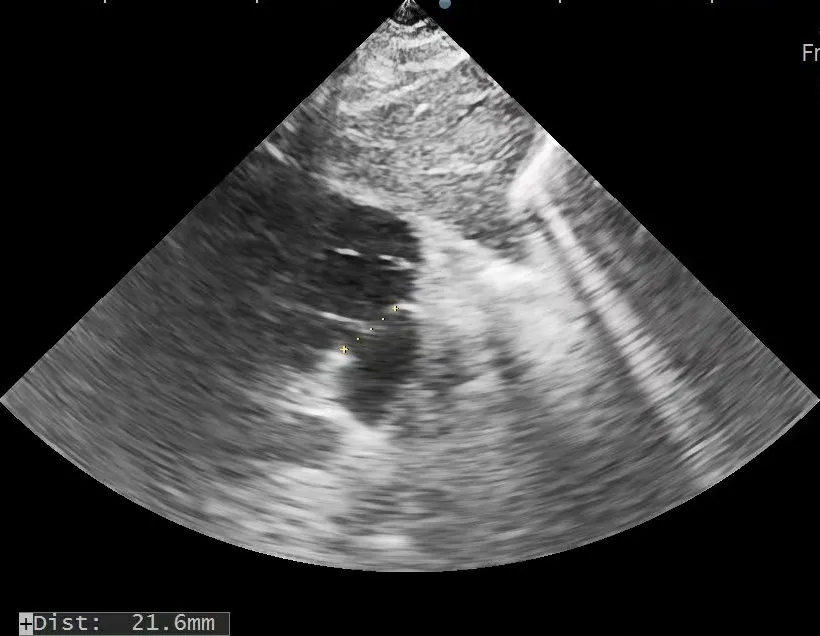

术前复测

多切面测量房间隔缺损直径为

20.5mm×22.0mm×21.6mm